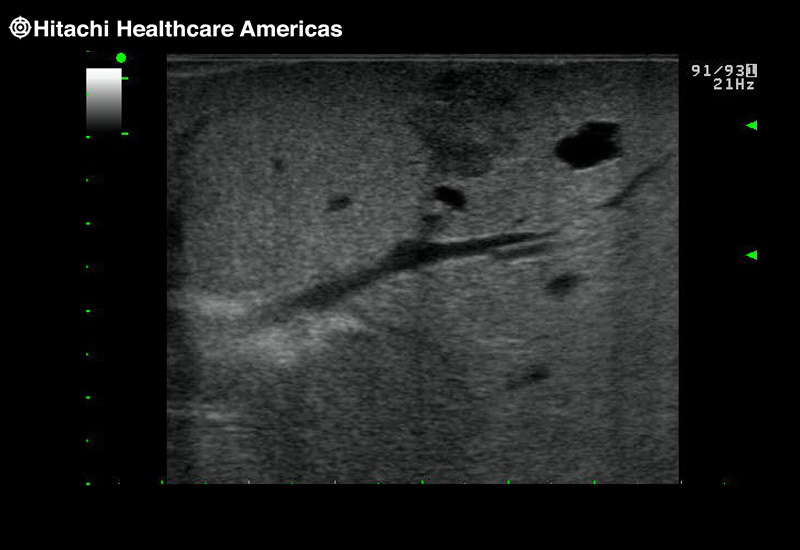

The Fujifilm Healthcare transducer utilizes the full benefits of the Wrist Articulation™ of the robotic instruments to capture real-time ultrasound imaging even at complex angles and difficult-to-reach areas.

Our smallest footprint allows for enhanced contact in tight spaces

Our newest probe, the L51K allows the surgeon access to difficult-to-reach areas that no other probe on the market can go. The unique design and proximal location of the attaching mechanism provides full wrist articulation and easier grasp and release.

Full wrist articulation with optimized functional length.

A critical function of robotic ultrasound guidance is tumor margin identification. Fujifilm's family of robotic probes all have the optimum location of the attaching mechanism that allows for full wrist articulation of the probe. The result is an increased confidence that the tumor margins have been completely identified.